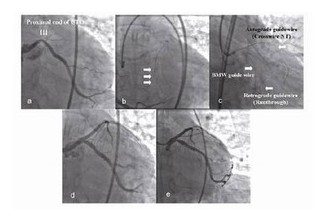

对侧冠脉造影在观察导引钢丝是否到达真腔和决定介入治疗方案时至关重要,CTO介入治疗之前仔细分析病史和观察冠脉造影有助于术者选择最佳的介入治疗方法,预测可能出现的问题及选择相应的处理措施。在CTO介入治疗中,通过对非闭塞血管造影,利用侧支血管灌注闭塞远段血管观察整个闭塞血管非常重要。尽管我们不需要对所有的CTO病变进行对侧冠脉造影,但是该方法对判断闭塞远端血管形态、闭塞段长度、闭塞血管的大致走向和导引钢丝前进方向正确与否起着非常重要的作用(图1)。